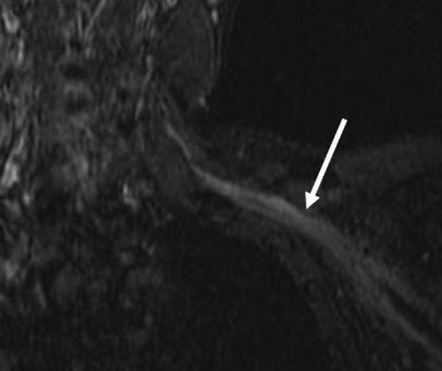

(Слева) STIR MPT, коронарная проекция (МР-нейрография). Асимметричное увеличение корешка CVIII нерва. выходящего между С7-Т1 позвонками.

(Справа) STIR MPT, коронарная проекция, другой пациент. Веретеннобразная шваннома с неоднородным гиперинтенсивным сигналом, расположенная в нижних отделах шеи. По сравнению с соседними нервами плечевого сплетения сигнал гораздо интенсивнее. При проведении тонкоигольной биопсии, благодаря которой удалось подтвердить диагноз, у пациента отмечалось подергивание руки.